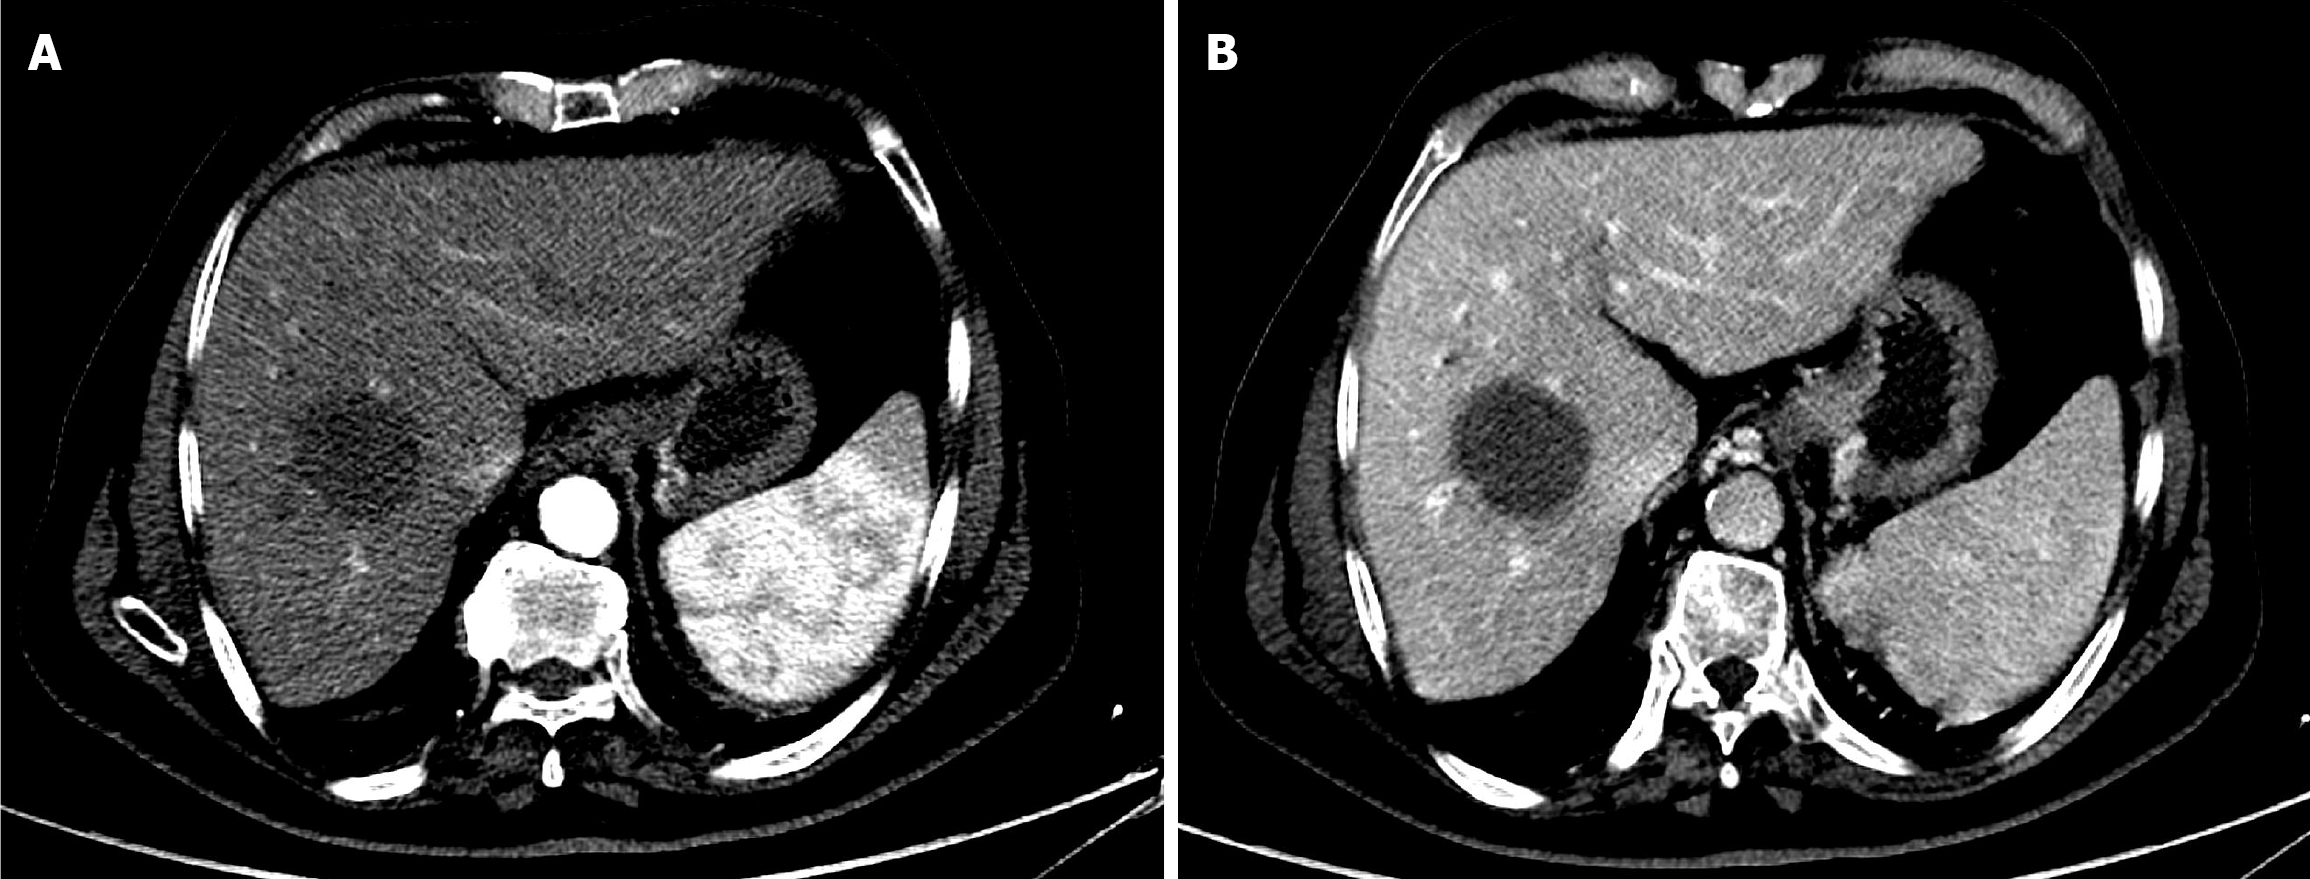

Figure 2 Baseline magnetic resonance imaging of the abdomen.

A: Arterial phase T1-weighted magnetic resonance imaging showed a large, well-defined, arterially enhancing hepatic mass; B: Delayed phase T1-weighted magnetic resonance imaging demonstrated washout of the lesion.